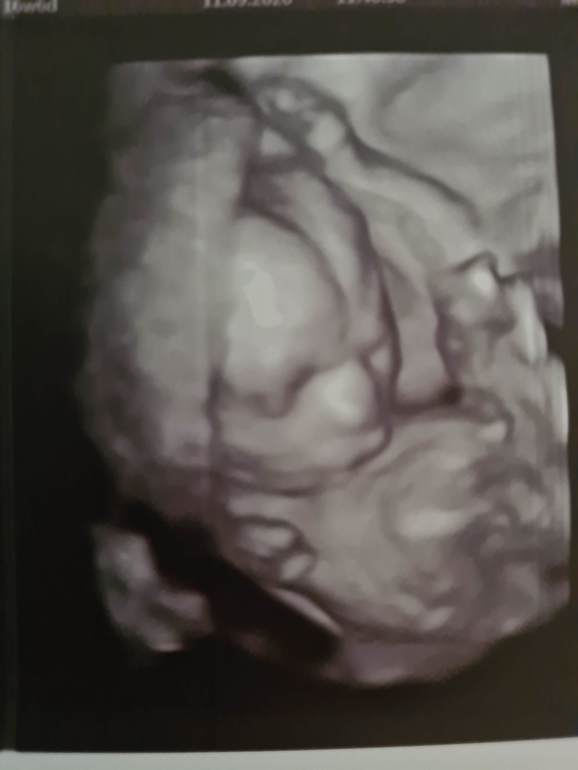

Нам в 3D показали малышку вот с такой пимпой на лице в 16+ недель:

Повторите обязательно узи, особенно круо там, где 3D могут посмотреть! А проколы сейчас не всегда назначают, чаще НИПТ.